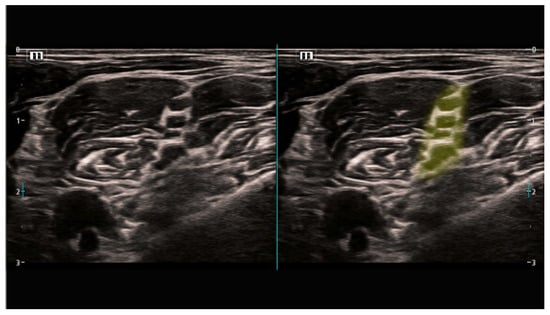

- Gungor, I.; Gunaydin, B.; Oktar, S.O.; Buyukgebiz, B.M.; Bagcaz, S.; Ozdemir, M.G.; Inan, G. A real-time anatomy identification via tool based on artifcial intelligence for ultrasound-guided peripheral nerve block procedures: An accuracy study. J. Anesth. 2021, 35, 591–594. [Google Scholar] [CrossRef]

- Erdem, G.; Ermiş, Y.; Özkan, D. Artificial intelligence-powered ultrasound guided regional nerve block in three patients: Case report. J. Turk. Soc. Algol. 2023, 35, 167–171. [Google Scholar] [CrossRef]

- Bowness, J.; Varsou, O.; Turbitt, L.; Burkett-St Laurent, D. Identifying anatomical structures on ultrasound: Assistive artificial intelligence in ultrasound-guided regional anesthesia. Clin. Anat. 2021, 34, 802–809. [Google Scholar] [CrossRef] [PubMed]